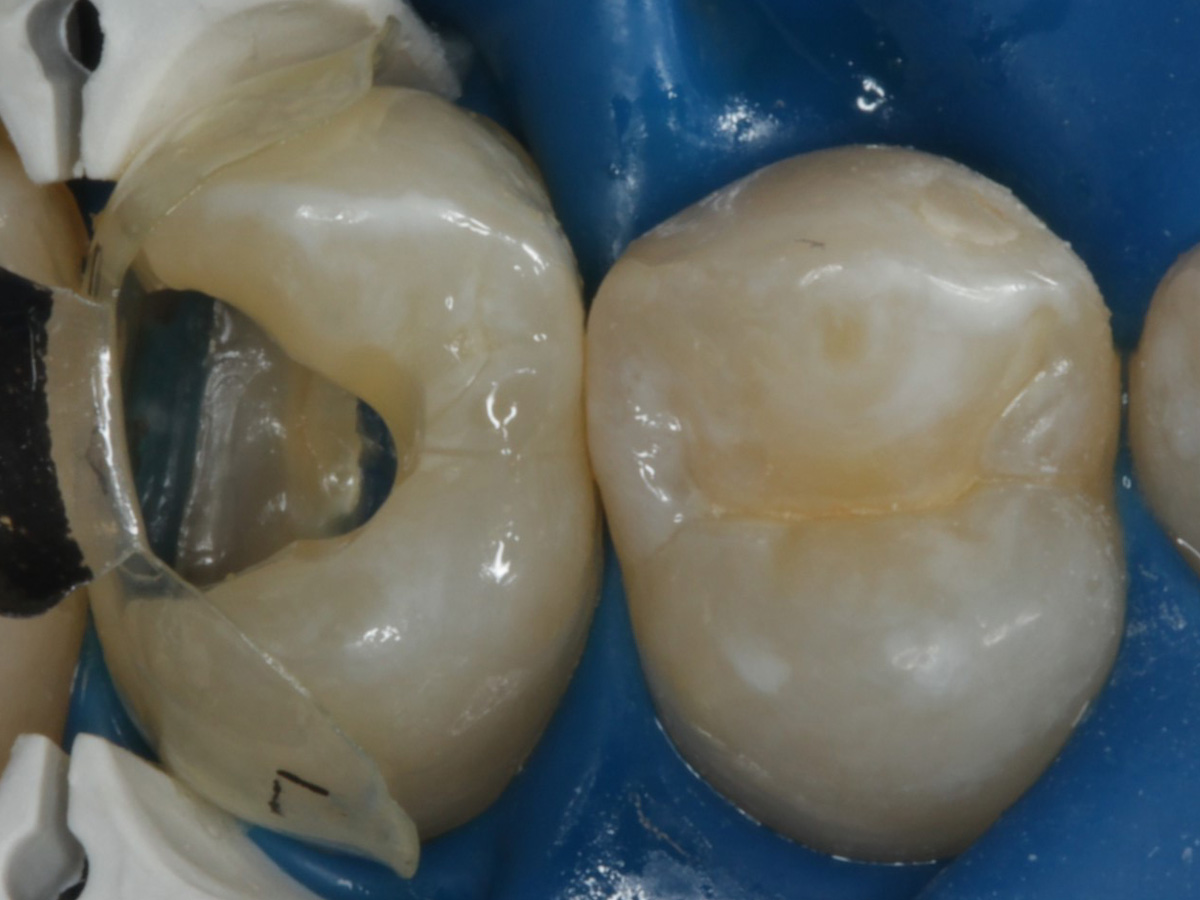

Abbildung 5

Height Indicator vor Auswahl der passenden Evolve Matrize nach Defektdarstellung, Kariesexcavation, Vitalexstirpation